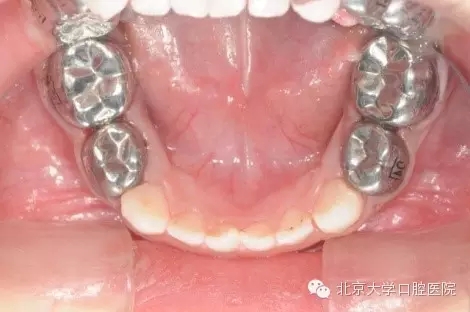

7為什么孩子的牙做了牙套?

全麻治療中醫(yī)生對缺損較大的后牙經(jīng)常會采用“預(yù)成冠”修復(fù)的方法,預(yù)成冠由不銹鋼制成,可以很好的恢復(fù)牙齒的外形并預(yù)防牙齒及充填體折斷,并不影響牙齒替換。

5.webp.jpg

6.webp.jpg